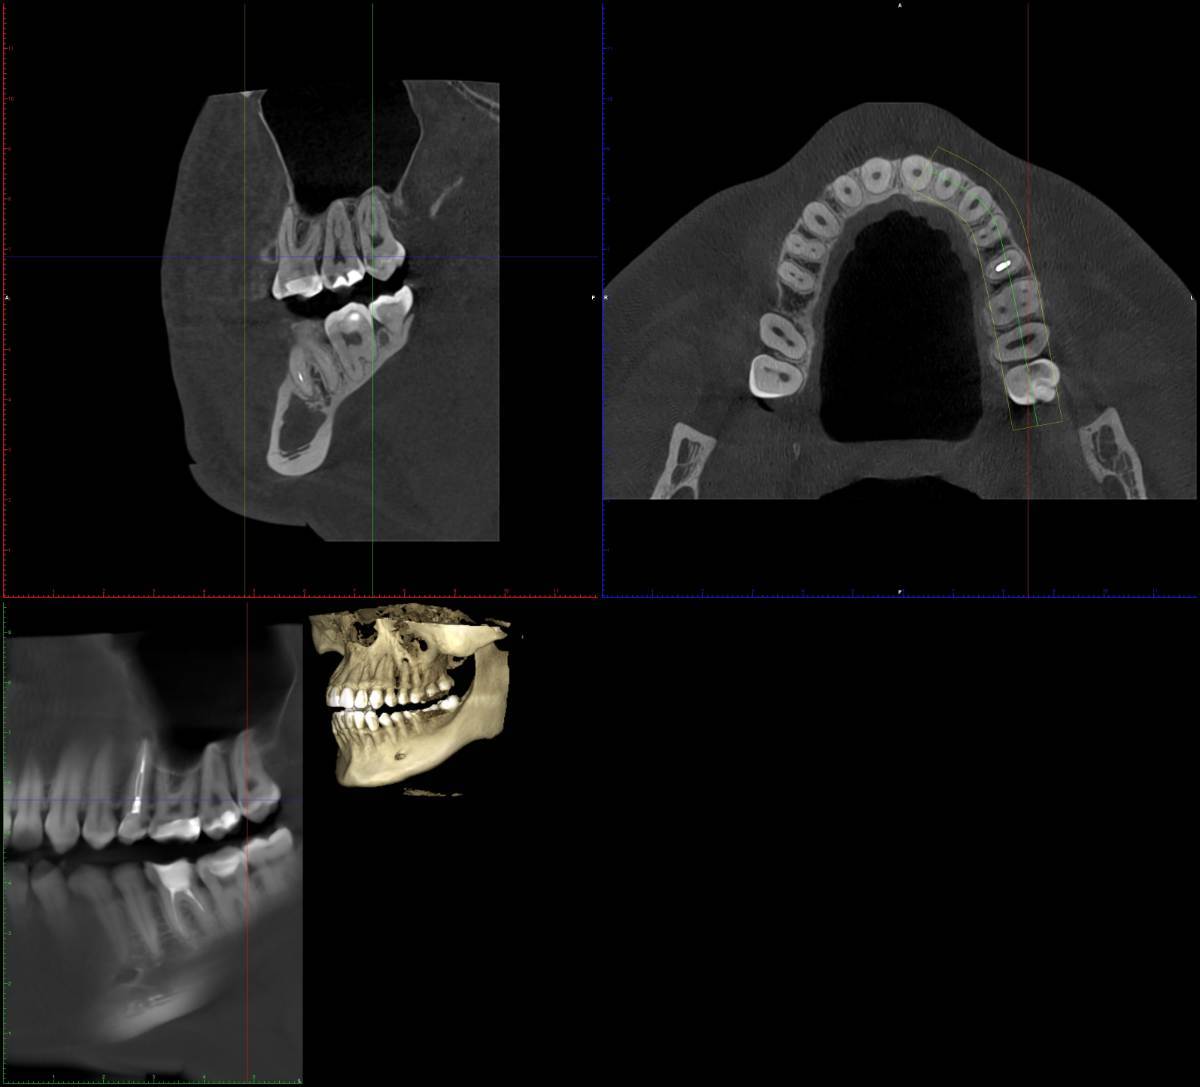

Л93 Опубликовано Понедельник в 18:57 Поделиться Опубликовано Понедельник в 18:57 (изменено) Доброго времени суток. Очень нужна консультация. В субботу припухла щека, заболела верхняя челюсть, конкретное место определить не удалось. Сегодня на осмотре у стоматолога вердикт, удалять 8ку и 5ку. Пошла на удаление, хирург внимательно изучив снимки, посоветовавшись с коллегой сказал, что 5ка под лечение, 8ка ещё и не вышла и с ней все в порядке. Прописал антибиотик и отправил к терапевту. Ближайшая запись к терапевту май. Действительно ли можно обойтись без удалении 5ки? Как срочно нужно заняться лечением если возможно вылечить 5ку? Заранее спасибо всем ответившим. Изменено Понедельник в 18:59 пользователем Л93 Ссылка на комментарий

Женька Опубликовано Понедельник в 19:36 Поделиться Опубликовано Понедельник в 19:36 Здравствуйте! Криминала не вижу по Вашему 25 зубу. Но это лишь один срез, не дающий полной картины. По 8... интересно посмотреть в полости рта. Потому что на снимке 6 лет назад она действительно не прорезалась, а вот на свежем вполне себе должна жевать с нижней 8. Ссылка на комментарий

Л93 Опубликовано Вторник в 09:59 Автор Поделиться Опубликовано Вторник в 09:59 @red_butler вчерашний снимок кт в первом сообщении Ссылка на комментарий

wladdX Опубликовано Вторник в 21:40 Поделиться Опубликовано Вторник в 21:40 (изменено) Скорее всего виновен 25 Изменено Вторник в 21:41 пользователем wladdX Ссылка на комментарий

red_butler Опубликовано 16 часов назад Поделиться Опубликовано 16 часов назад Здравствуйте, требуется повторное лечение корневых каналов пятого зуба. почитайте эту тему Ссылка на комментарий